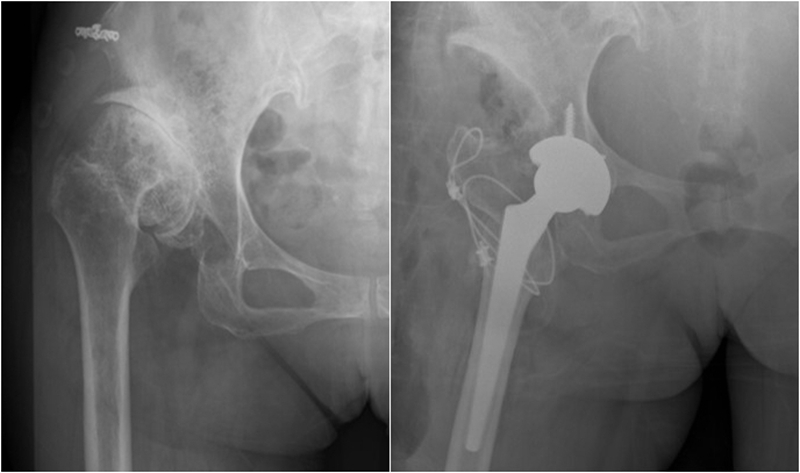

Ⅱ、股骨颈畸形---髋内外翻,offset异常

(1)颈干角偏小(<120°)——髋内翻

髋内翻,颈干角小,偏心距较大,选择high-Offset假体,以维持外展肌张力。

(2)颈干角过大(>140°) ——髋外翻

髋外翻多见于DDH,难度在于股骨距内侧皮质阻挡假体完全坐入髓腔,强行打击造成股骨距骨折。